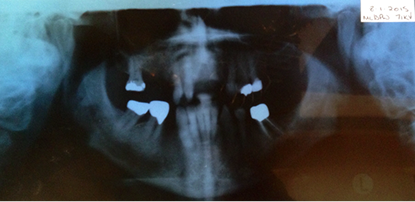

OPG

Maxillary CT scan confirms that there is 3.5mm (maximally) of ridge present

UL anterior region